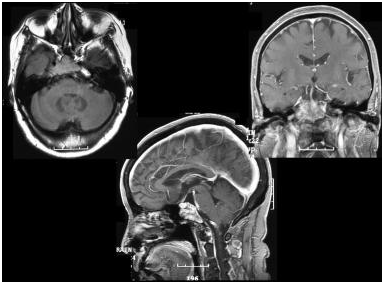

颅咽管瘤是儿童下丘脑和鞍上区较常见的病变,外胚叶形成的颅咽管残余的上皮细胞,发展起来的一种常见的胚胎残余组织肿瘤,是颅内较常见的先天性肿瘤,常伴有垂体功能损害。由...

对于 颅咽管瘤 ,很多人可能并不陌生,这是一种常发于儿童的颅内肿瘤,是由颅咽管残余上皮生长的肿瘤。胚胎3周时,外胚叶首端腹侧的部分上皮向内凹陷生长,成一盲管,称为腊特...